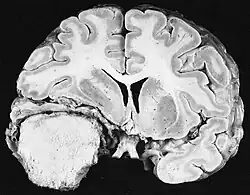

Glioblastome

Les tumeurs des cellules gliales les plus courantes et les plus malignes sont les glioblastomes. Ils consistent en une masse hétérogène de cellules d'astrocytome peu différenciées principalement chez l'adulte. Ils surviennent généralement dans les hémisphères cérébraux, plus rarement dans le tronc cérébral ou la moelle épinière. Sauf dans de très rares cas, comme toutes les tumeurs cérébrales, elles ne s'étendent pas au-delà des structures du système nerveux central.

Le glioblastome peut provenir d'une forme diffuse (II. grade) ou un astrocytome anaplasique (III. grade) développer. Dans ce dernier cas, il est dit secondaire. Cependant, lorsqu'elle survient sans antécédent ni signe de malignité antérieure, on parle de maladie primaire. Les glioblastomes sont traités par chirurgie, radiothérapie et chimiothérapie. Ils sont difficiles à guérir et rares sont les cas qui survivent au-delà de trois ans.